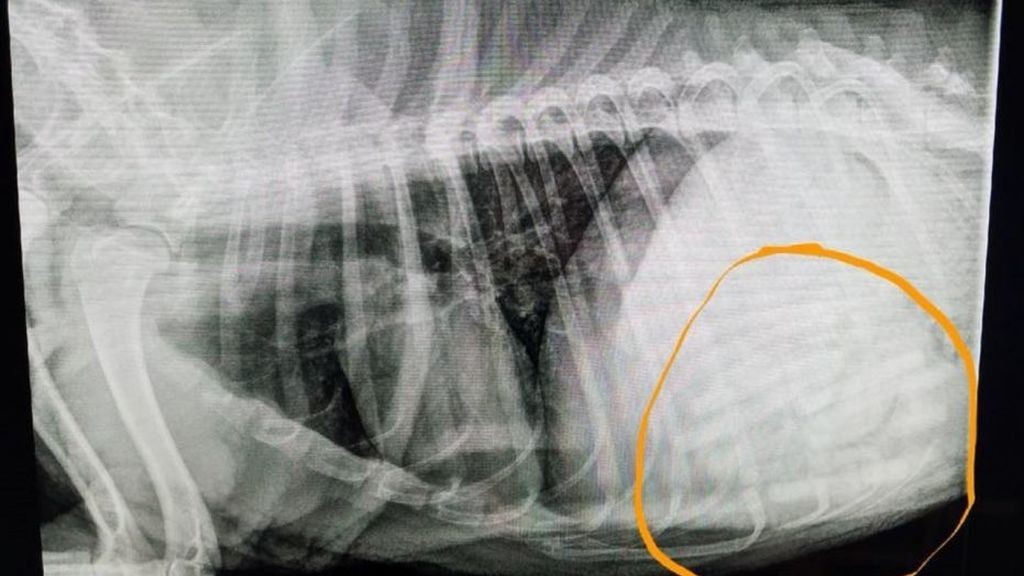

En un primer momento, cuando el realizaron una radiografía, creyeron que tenía entre 7 y 9 chupetes. Pero cuando le intervinieron descubrieron que eran 21, según recoge Fox News.